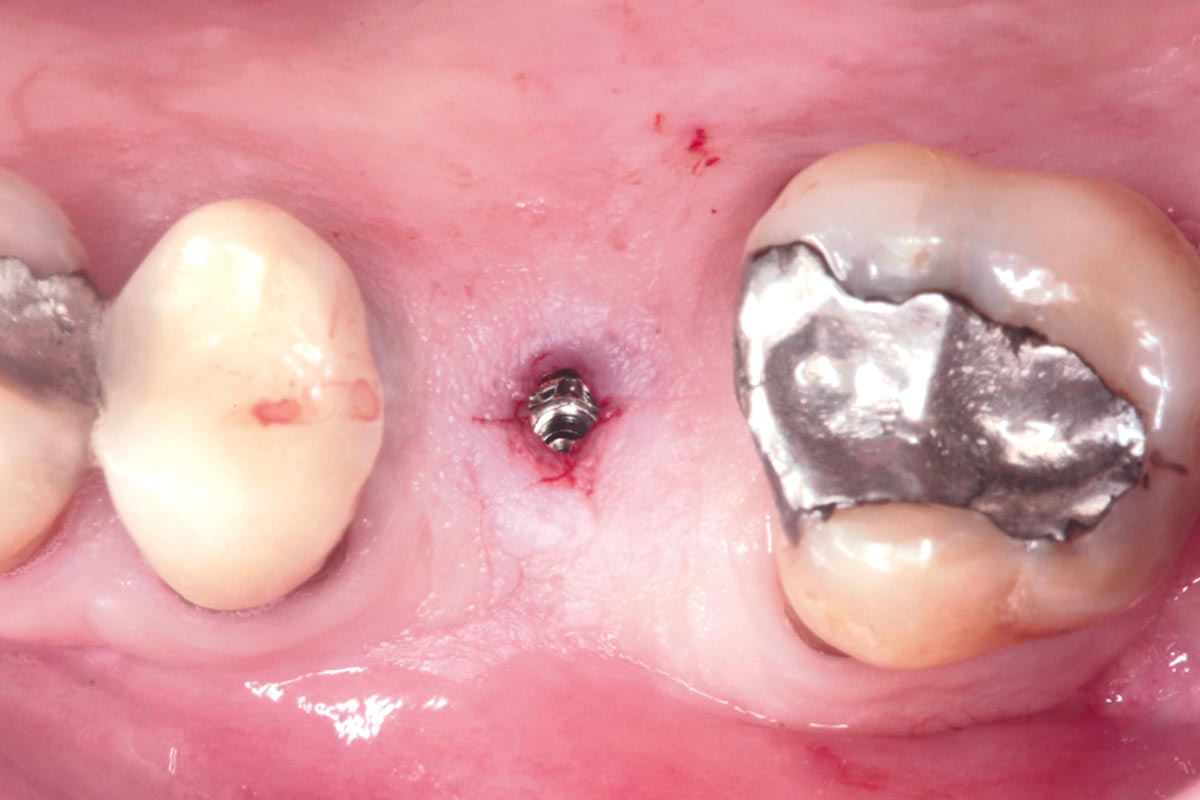

27/35 - Mini-invasive second stage, in order to save the keratinized mucosaMaxillary sinus cyst removal using the Crocodile Technique and subsequent lateral sinus lift - Dres. C. Scognamiglio and A. Perucchi